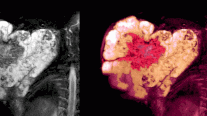

يتسبب الالتهاب المفصلي العظمي في تكسير الغضروف؛ وهو نسيج قوي ومنزلق يغطي نهايات العظام عند مكان تكوُّن المفصل.